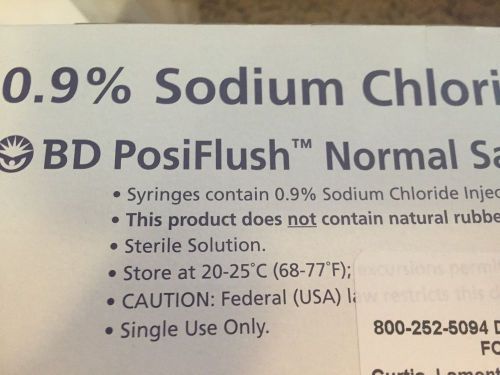

50 PosiFlush 10cc BD Pre-Filled Saline Syringe Flush 0.9% Sodium Chloride